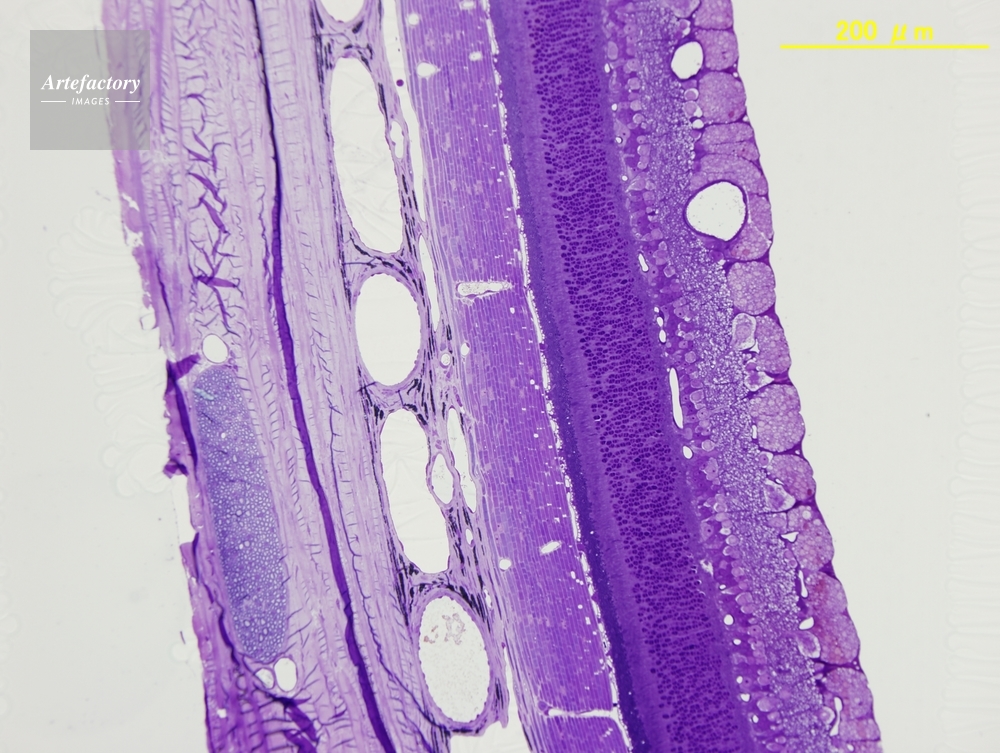

| 作品タイトル | ネコ,網膜 | モデルリリース | なし | |

| 作家 | OLYMPUS CORPORATION Technolab | プロパティリリース | なし | |